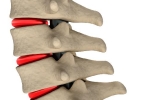

• 腰椎盘突出术后卧床多久

腰椎盘突出术后卧床多久

腰椎间盘突出术后一般需要卧床1-3天,实际时间受到手术方式、神经压迫程度、术后恢复情况、患者年龄及基础疾病等因素影响。1、手术方式:微创椎间孔镜手术创伤小,通常术后24小时可下床活动;传统开放手术因需修复椎 ...